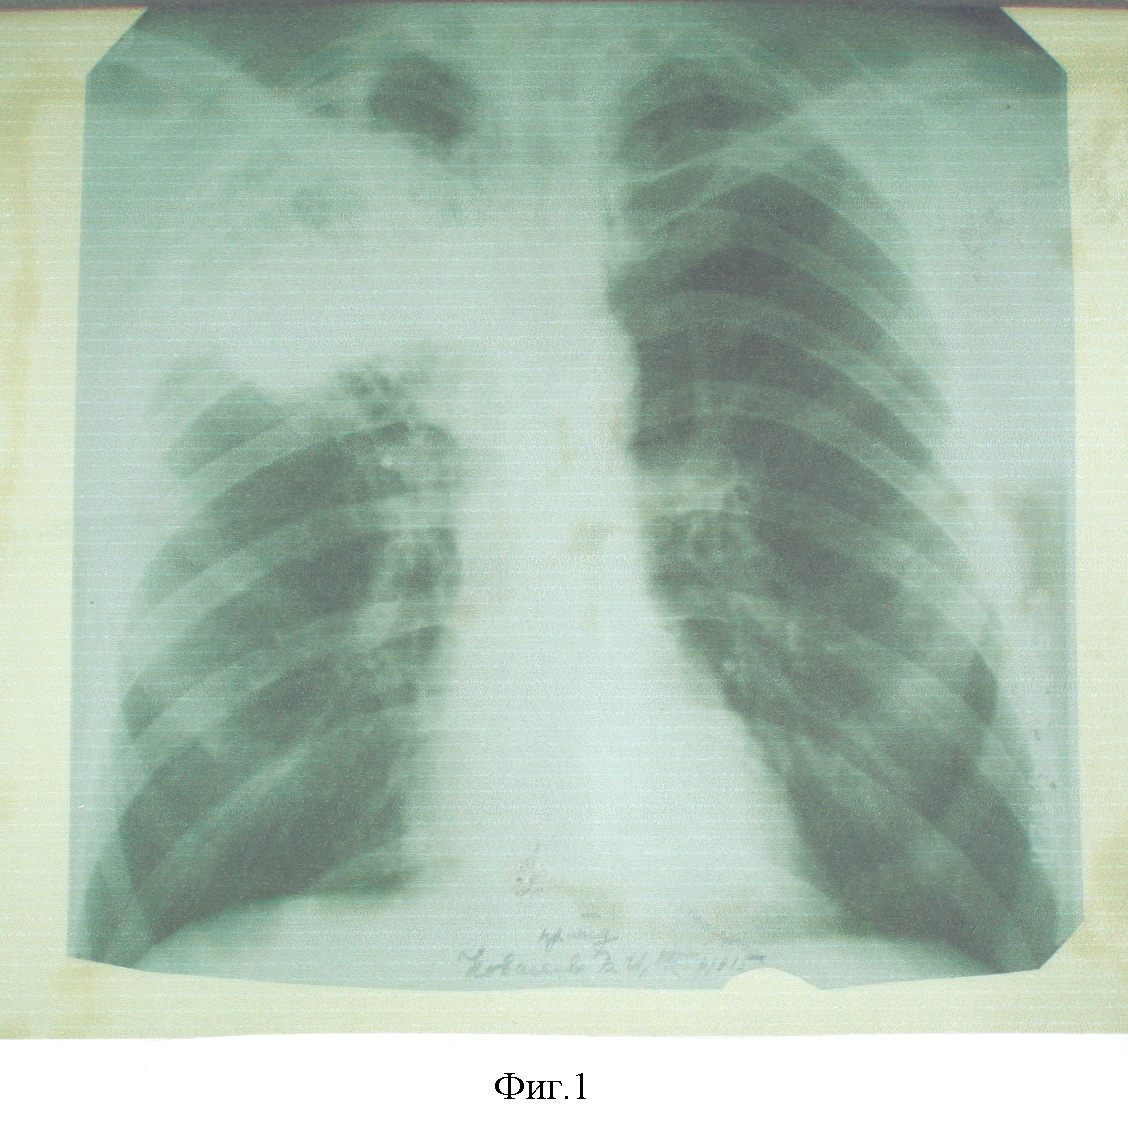

Больной К., 50 лет, ист. бол. №22640Ф направлен в РНИОИ в ноябре 2005 г. Цимлянским ПТД после безуспешного лечения туберкулеза правого легкого в течение 3-х лет. При поступлении жаловался на боли в грудной клетке, слабость, потливость, похудание, одышку при физической нагрузке. Из анамнеза выяснено, что заболевание началось с повышения температуры тела до 38°С с апреля 2002 г. После флюорографического обследования поставлен диагноз очаговоинфильтративный туберкулез верхней доли правого легкого. В течение года лечился в противотуберкулезном диспансере. Затем в течение 2-х лет находился под диспансерным наблюдением фтизиатра. В августе-сентябре 2005 г. в связи с прогрессированием заболевания повторно лечился в противотуберкулезном диспансере. В связи с отсутствием положительного эффекта от лечения, ухудшением общего состояния, появлением боли в грудной клетке, одышки, слабости, потливости, похудания самостоятельно обратился в РНИОИ, был госпитализирован в отделении торакальной пластической хирургии (см. фиг.1).

Фиг.1. Больной К-в. Обзорная рентгенограмма до начала лечения.

Где с ноября 2005 г. по февраль 2006 г. проведено 3 курса АГХТ с интервалом между курсами – 1 месяц, по вышеописанной методике. Суммарно за 3 курса получил цисплатина – 600 мг; доксорубицина – 40 мг, циклофосфана – 6000 мг. Уже после I курса отмечена полная регрессия клинических симптомов, а к концу III-го курса почти полное рассасывание патологического очага в правом легком, подтвержденном рентгенологически (см. фиг.2 и 3).